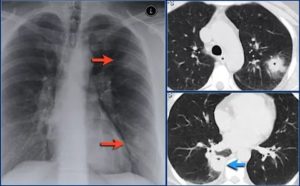

Рентгенограмма показывает усиление рисунка бронхиального дерева, сужение просвета бронхов, образование бронхоэктаз.

На рентгенологических снимках расширения видны даже в мелких бронхах, хорошо просматриваются их патологические сужения, множественные бронхоэктазы.